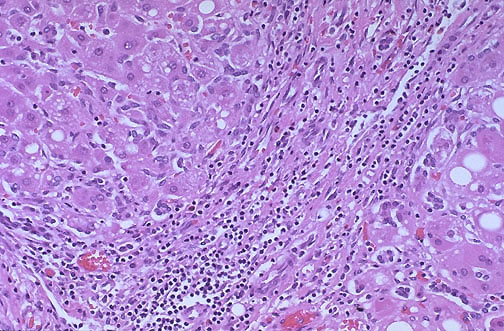

Image 8.2

The medium power appearance of the liver is seen here.